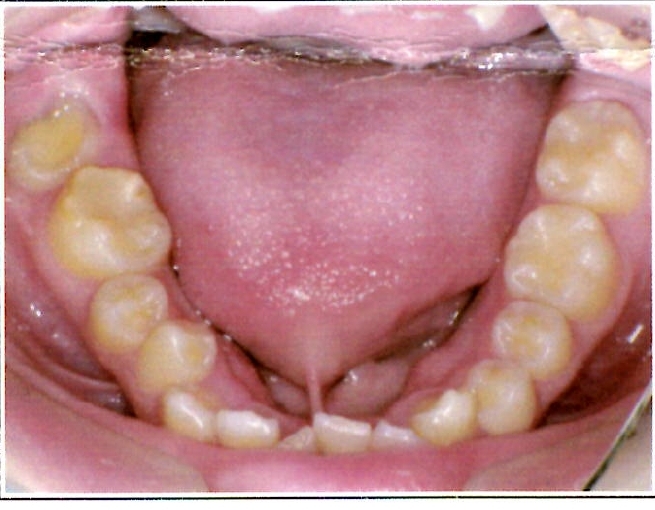

| 主訴・治療前の状態 | 著しい叢生(歯並びのガタガタ)があり、また6歳臼歯(第一大臼歯)が破折していた状態でした。 |

| 治療内容 | 通常の抜歯矯正では第一小臼歯(4番)を抜歯することが多く、その方が治療期間を短縮できますが、小川さんの場合は破折していた6歳臼歯を抜歯し、そのスペースを活用して歯列を整えました。これにより、健康な歯の本数を維持しながら矯正治療を行うことができました。 |

| 治療結果 | 治療前と比較して歯並びが大きく改善し、見た目も大幅に良くなりました。患者様にも大変喜んでいただけた症例です。 |